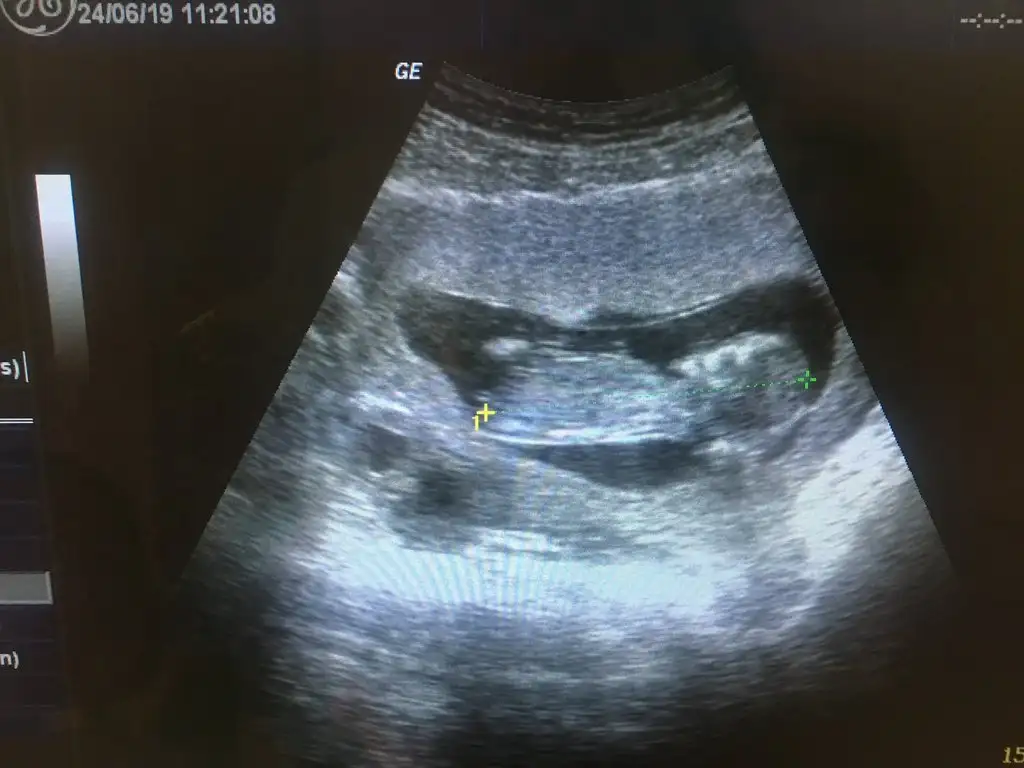

Kızlar merhaba Ben de 14. Haftadayım cinsiyetini henüz öğrenmedim tabi merak ediyorum ilk hamileliğim İnternette bir yazıya denk geldim nub teorisine göre cinsiyet belirleme çoğunlukla doğru çıkıyormuş.Nub teorisi ultrasondaki minnoşların iki bacak arasındaki çıkıntı hafif dik ise erkek parelel ise kızmış tabi ben ultrason görüntüsünü evirdim çevirdim anlamadım pek internette örnekleri var bir bakabilirsiniz belki sizin minnoşların daha net görünür

Yaa ne güzel Allah bağışlasın Ben çözemedim henüz Çarşamba kontrolüm var ama söyler mi bilmem ultrason görüntüsü böyle belki siz anlarsınız ben anlayamadım